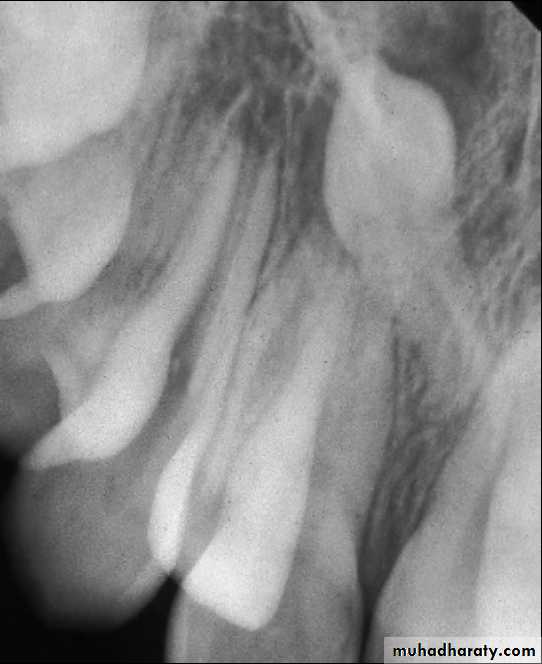

Supernumerary teeth and odontomes often must be removed as they can delay eruption or impede orthodontic tooth movement, particularly of maxillary incisors. If supernumerary teeth are removed from the path of eruption, the underlying teeth will often erupt given sufficient space. It has been estimated that this will occur spontaneously in approximately 60% of cases.An inverted supernumerary tooth—usually referred to as a mesiodens if it occurs in the incisor region. It should only be removed if there is a genuine clinical indication.

Odontomes are less common than supernumerary teeth, although the differentiation between the two is considerably blurred. Odontomes may be simple (tooth-like), compound (multiple tooth-like) or complex composite (containing elements of the tooth germ in a disorganized fashion). Like unerupted teeth, odontomes need only be removed if there are clinical indications (as infection, they are obstructing eruption of other teeth, and esthetic problems).